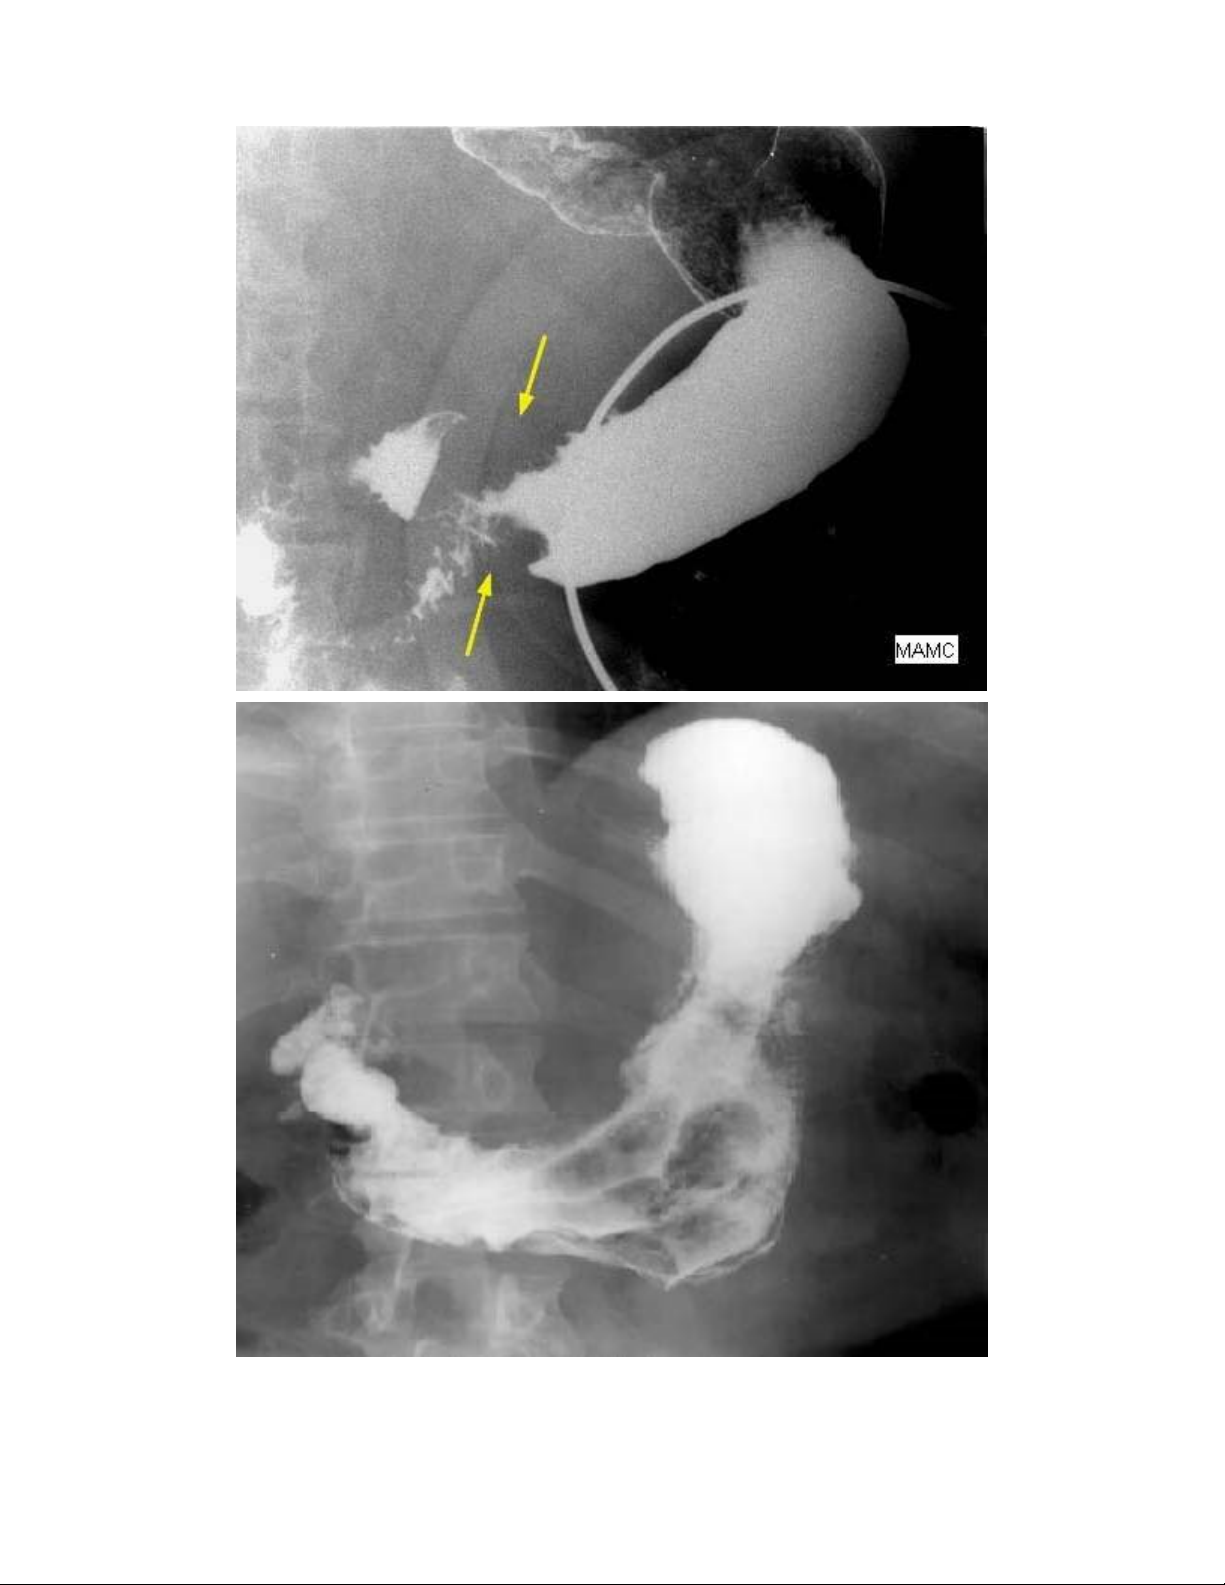

X-quang dạ dày với Barium: là phương tiện chẩn đoán hình ảnh cổ điển (hình 1). X-quang dạ

dày với Barium không phân biệt ung thư dạ dày dạng loét với loét dạ dày lành tính. Mặc dù giá

trị chẩn đoán ung thư dạ dày của X-quang dạ dày có thể lên đến 90%, X-quang dạ dày chỉ nên

được chỉ định cho những BN có triệu chứng nghi ngờ nhưng không có các yếu tố nguy cơ.

Hình 1- Hình ảnh ung thư dạ dày vùng hang vị (A) và hang-thân vị (B) trên X-quang dạ dày